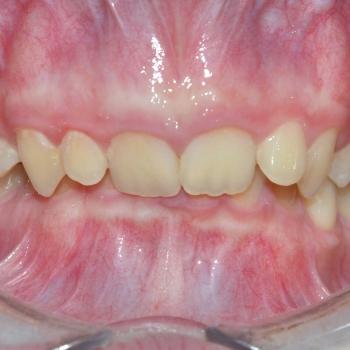

Balázs és édesanyja konzultáció céljából keresett fel, hogy egyértelműen kiderüljön számukra szükséges-e a fogszabályozó kezelés vagy sem. Már rögtön az első vizsgálat alkalmával fény derült több olyan problémára is, melyek fogszabályozást igényelnek. Ilyen volt például a súlyos mélyharapás, a hátrafelé dőlő felső metszők, illetve az Angle II. osztályú harapási eltérés is. A mintavétel, a röntgenek és a fotók kiértékelése után további problémaként merült fel a felső fogív szűkülete és a kismetszők méretaránytalansága, azaz a túlzott keskenységük.

A kezelést Quadhelix fogszabályozóval kezdtük el a felső fogív tágítása érdekében. Ezután került felragasztásra az alsó és felső fogívre a Balázs és szülei által kiválasztott fém önligírozó fogszabályozó. Ezen túlmenően Bite turbo harapásemelő segített a mélyharapás, intermaxillaris gumihúzás pedig az Angle II. osztályú harapási eltérés korrigálásában. A fogak méretaránytalansága miatt a kezelés végén a kismetszőket tömőanyaggal építettük fel, hogy a tökéletes harapáshoz résmentes fogazat társuljon. A fogak felépítéséhez az adott fogakat nem kell megfúrni, a tömőanyag kizárólag ragasztásos módszerrel rögzül, így nem károsodik a fogzománc.